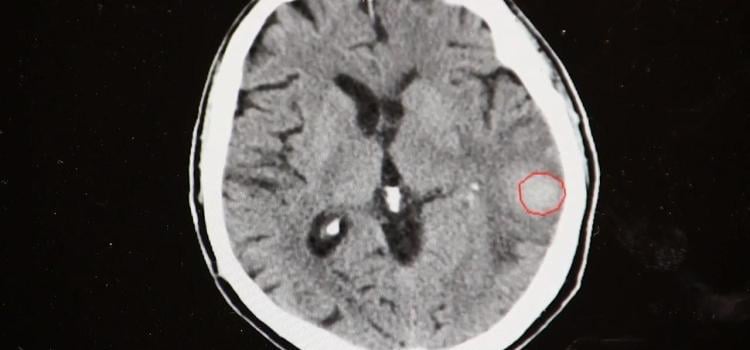

Artificial intelligence (AI) has found a unique niche to help automate the activation of acute care teams for pulmonary ...